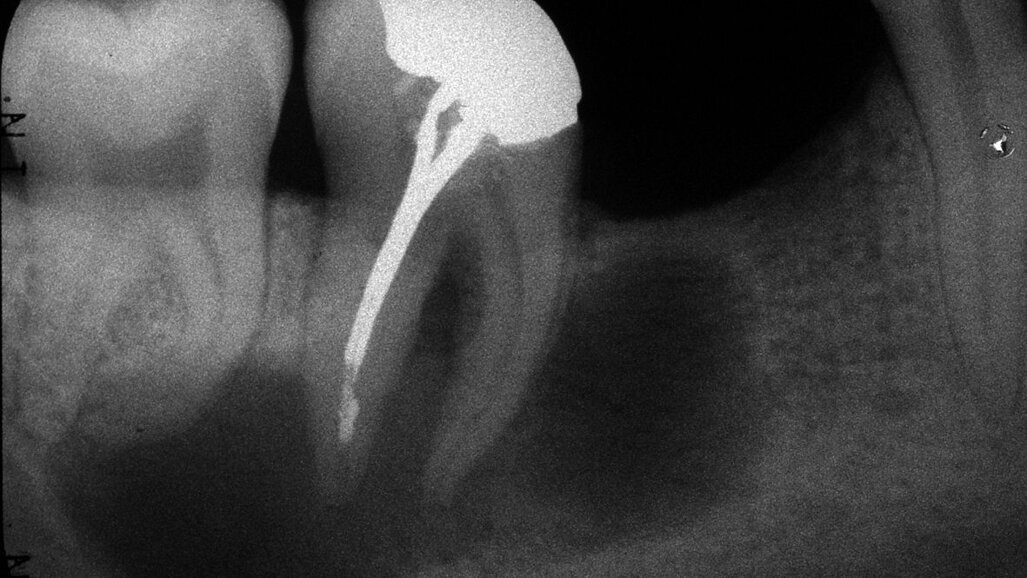

La 48 n'était pas traitée alors que la 47 avait un amalgame et une obturation de racine antérieure. Les tests de sensibilité ont révélé que la 48 répondait positivement, alors que la 47 donnait une réponse négative. Il n'y avait pas de sondages supérieurs à 3 mm. Il n'y avait pas de gonflement ou d'expansion vestibulaire de l'os et les dents n'étaient pas sensibles à la percussion ou à la palpation. Un grande lésion péri-apicale multiloculaire de 25mm par 10mm a été notée pour être associée avec les 47 et 48 (Fig. 1).

Un diagnostic provisoire de parodontite apicale chronique a été établi. La cause probable de la lésion était des bactéries intra-radiculaires. Au cours des dernières années, la majorité des dentistes a suggéré que le traitement de choix était d'extraire la dent et, éventuellement, d'énucléer la lésion. Il est important de se rappeler que l'on ne peut pas diagnostiquer si une lésion est odontogène ou non odontogène, par la seule radiographie. Il existe deux types de kystes : les vrais kystes et les granulomes. Les granulomes sont connectés au système racinaire et on s'attend à une guérison après un traitement endodontique conventionnel. Théoriquement, les kystes vrais sont indépendants de l'espace canal-racine et ne peuvent guérir par le traitement de racines seul. (Beaucoup de preuves suggèrent que la taille de la lésion n'influence pas le résultat de la guérison, bien qu'il puisse être vrai que plus grande est la lésion, plus grande est sa probabilité d'être kystique.) Le traitement recommandé pour le patient était le retraitement des racines avec examen dans six mois pour évaluer la guérison. Il y avait une possibilité évidente d'infection dans les canaux mésiaux non traités, tandis que les canaux distaux avaient eu des traitements techniquement insuffisants. (Fig. 1).

Lors d'une visite ultérieure, aucun symptôme n'a été enregistré et les canaux ont été irrigués avec de l'hypochlorite de sodium et de l'EDTA pour éliminer tout l'hydroxyde de calcium restant et tous débris organiques et inorganiques. Les canaux ont ensuite été obturés avec une technique de condensation verticale chaud à l'aide du System B Obtura (SybronEndo). Il y a eu quelques extrusions de ciment, ce qui n'affecte pas le résultat du traitement, mais peut retarder la guérison (Fig. 2).

Les progrès modernes, tels que le microscope opératoire, l'instrumentation NiTi, l'irrigation par ultrasons et les techniques d'obturation thermoplastique, se combinent avec l'utilisation traditionnelle de la digue et le débridement chimique à l'aide d'hypochlorite de sodium et d'hydroxyde de calcium pour obtenir ces taux de réussite exceptionnels (fig. 1 & 3).